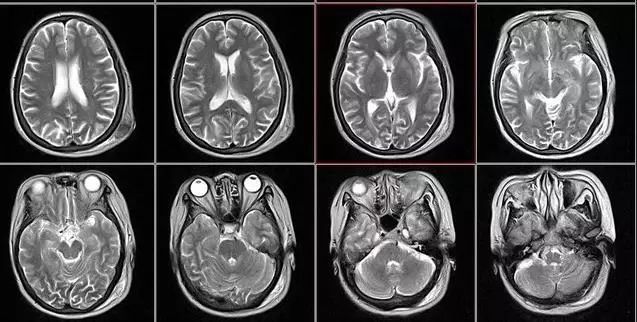

核磁共振:摇一摇再看

0.webp (2).jpg

核磁共振机使用较强大的磁场,使人体中所有水分子磁场的磁力线方向一致,这时磁共振机的磁场突然消失,身体中水分子的磁力线方向,突然恢复到原来随意排列的状态。简单说就相当于用手摇一摇,让水分子振动起来,再平静下来,感受一下里面的振动。所以,核磁共振(MRI)也被戏说为是摇摇看的检查。